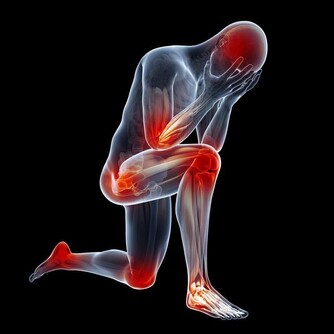

4、腰痛

腎臟的位置在腰部的脊椎兩側,

所以腎臟有病時,會感到腰痛。